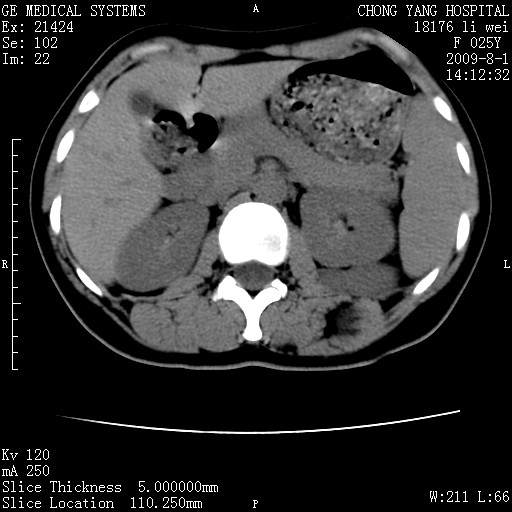

以下是引用pujunzhi在2009-8-1 20:23:00的发言:[br]胸椎旁及背部肌间良性病变,范围广,边界清,沿肌间生长,考虑淋巴管瘤、血管瘤,建议增强扫描。